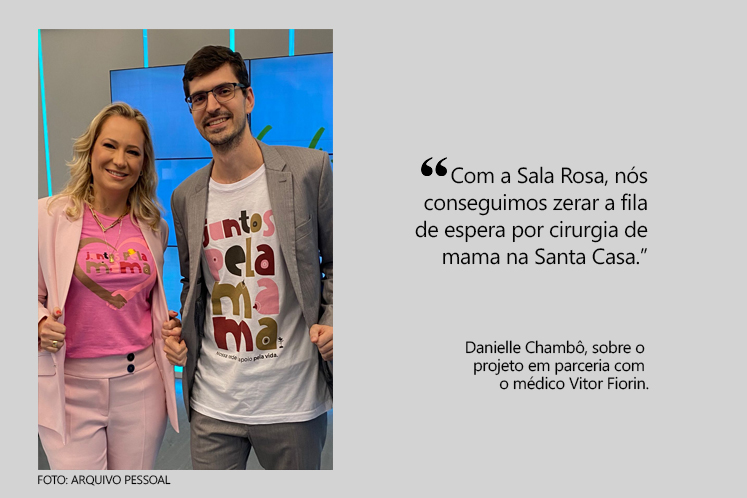

Em outubro, mês da campanha 'Outubro Rosa' de conscientização sobre o câncer de mama, o Espírito Santo comemora a ampliação do acesso à mamografia, que agora estará disponível para todas as mulheres a partir dos 40 anos.